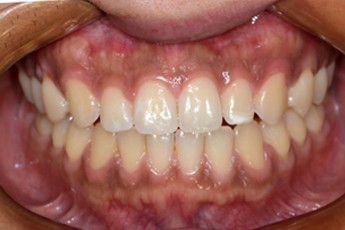

BEFORE & AFTER

- 과개교합교정